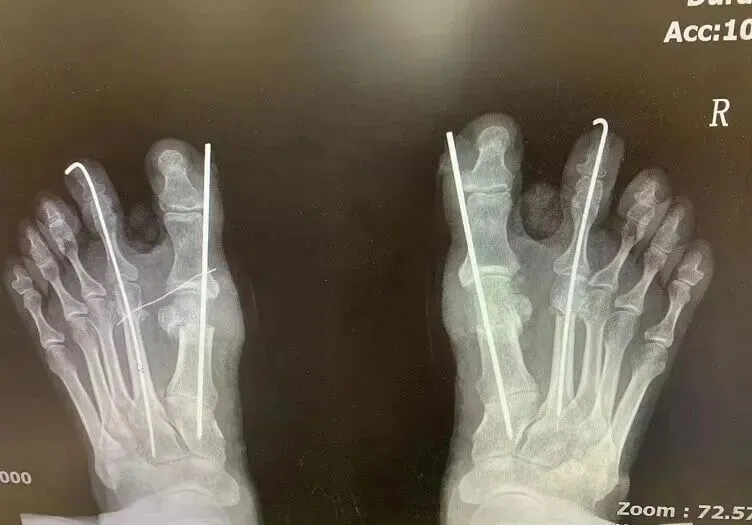

术后X光片参考